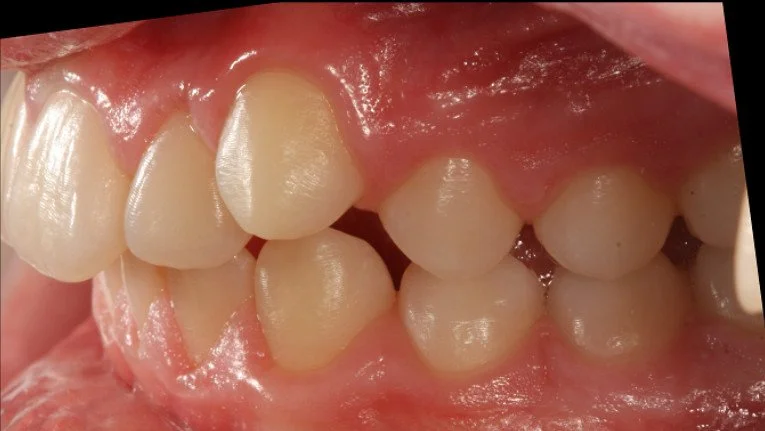

AFTER

Trattamento con 4 estrazioni di una malocclusione di classe II con proclinazione degli incisivi superiori e inferiori.